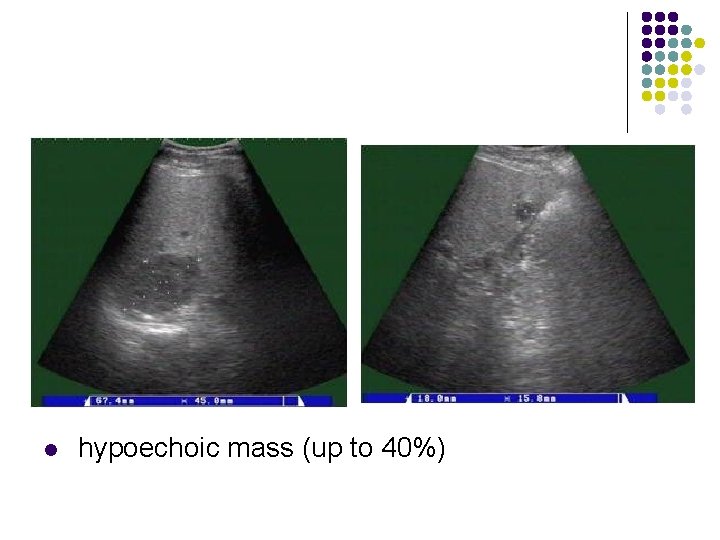

Ultrasonic features of Hepatic hemangioma l l l Uniformly hyperechoic mass(60 -70%) Inhomogeneous hypoechoic mass (up to 40%) Homogeneous(58 -73%) /heterogeneous May show acoustic enhancement(37 -77%) Unchanged in size/appearance(82)on 1 -to-6 year follow-up No Doppler signals/signals with peak velocity of <50 cm/cm

l hypoechoic mass (up to 40%)